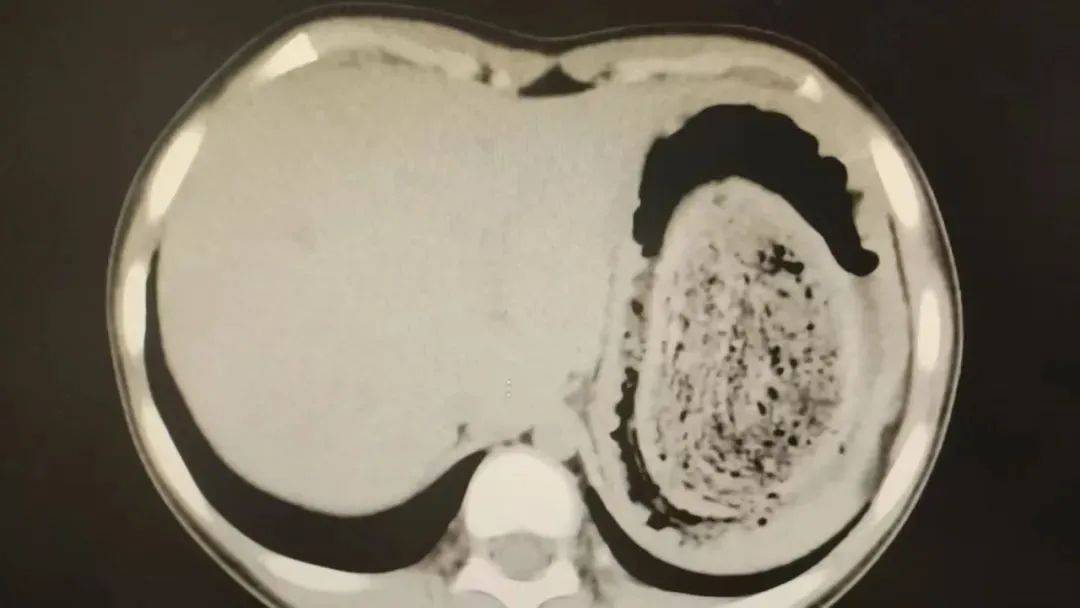

在胃镜帮助下,妮妮胃里的情况逐渐明了皇冠信用网登2。一个滚圆黑色的毛发球混合着食物残渣占据整个胃腔,这些头发相互缠绕形成一个实心的“发石”,此外胃里还有一个鸡蛋大小的溃疡。

“发石”混杂着食物残渣,就像一个黑色的小西瓜皇冠信用网登2。由于整个“发石”体积太大,为避免损伤胃壁,医生借助手术工具将“发石”切割、分解,再小心翼翼地分块取出。整场手术持续2个多小时,最终取出4斤头发碎片。

10岁女孩园园(化名)因持续3天的上腹痛伴呕吐被紧急送医皇冠信用网登2。影像学检查结果显示,她的胃部存在一个巨大的团块状阴影,初步怀疑为异物堵塞。据家长回忆,园园从1年前开始就有偷偷吃头发的习惯,但家人并未重视,直到这次症状严重才意识到问题的严重性。

2024年10月,11岁女孩欢欢(化名)因腹痛难耐紧急送到医院,而就在两个月前,欢欢的父母发现她在拔自己的头发,偷偷吃掉皇冠信用网登2。经检查,医生发现她胃腔和肠管里有大块的毛絮状结石,几乎占据整个胃部。最终,一块长38厘米、宽15厘米、厚10厘米的毛发结石被取出。